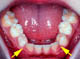

Sieht unauffällig aus, aber... Ihr Zahnarzt wird es sicher erkennen: Da, wo die Pfeile sind, sollten die Eckzähne einmal durchbrechen. Sie haben aber überhaupt keinen Platz.